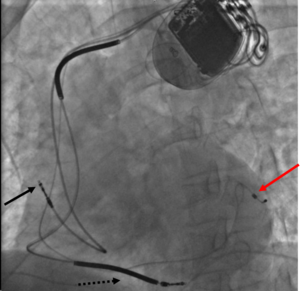

يوجد نوعان من المنظمات القلبية، المنظم ذو غرفة واحدة والمنظم ذو غرفتين والطبيب هو الذي يحدد نوع المنظم المراد تركيبه للمريض حسب ملاءمته لحالته. ومعظم المنظمات الحديثة تكون مبرمجة بحيث يمكنها اكتساب الكثير من الصفات العادية مثل معدل التنبيه وقوة الومضة الكهربائية ويمكن تعديل هذه الصفات لتتناسب مع المتطلبات الخاصة لكل مريض. وهذه المنظمات الحديثة يمكن التحكم في عملها بجهاز خارجي ((المبرمج)) فيمكن تغيير صفاتها كما هو الحال عند التحكم في جهاز التلفزيون عن بعد، وعليه فيمكن للطبيب تغيير عمل المنظم حسب حاجة المريض دون الحاجة لتغيير هذا المنظم.

2 - المنظم ذو غرفتين: هذا النوع من المنظمات يكون متصل بالقلب بواسطة سلكين كهربائيين يتصل أحدهما بالغرفة العليا (الأذين) والآخر بالغرفة السفلي للقلب (البطين) وهذه المنظمات بإمكانها الإحساس بالإنقباض الطبيعي للقلب وتنبيه إحدى أو كلا الغرفتين. معظم المرضى الذين يحتاجون لهذه المنظمات يكون لا يزال لديهم بعض التنبيهات القلبية الطبيعية، وفي هذه الحالة يقتصر عمل منظم القلب على الاحتياج الفعلي حسب حاجة القلب.

وأثناء عملية التركيب هذه يقوم الطبيب بمراقبة حركة السلك من خلال شاشة تلفزيونية تحت الأشعة السينية لوضع السلك الكهربائي في مكانه المحدد بالقلب.